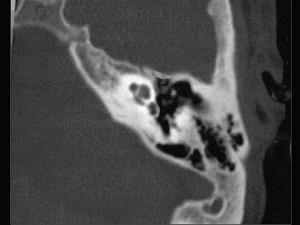

问题 一男性患者,持续左耳流脓10年,检查示左侧35dB下降的传导性耳聋,如图分别为他的鼓膜外观和颞骨CT检查,可诊断为 ( )

选项 A、急性中耳炎 B、以上都不是 C、慢性化脓性中耳炎骨疡型 D、慢性化脓性中耳炎胆脂瘤型 E、慢性化脓性中耳炎单纯型

答案 D